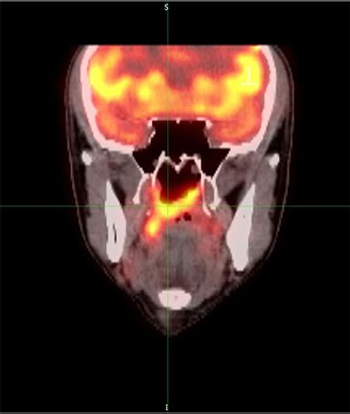

Researchers in China have found that the use of [18F] fluorodeoxyglucose PET/CT detected a greater number of distant metastases than conventional work-up imaging in patients with nasopharyngeal carcinoma.